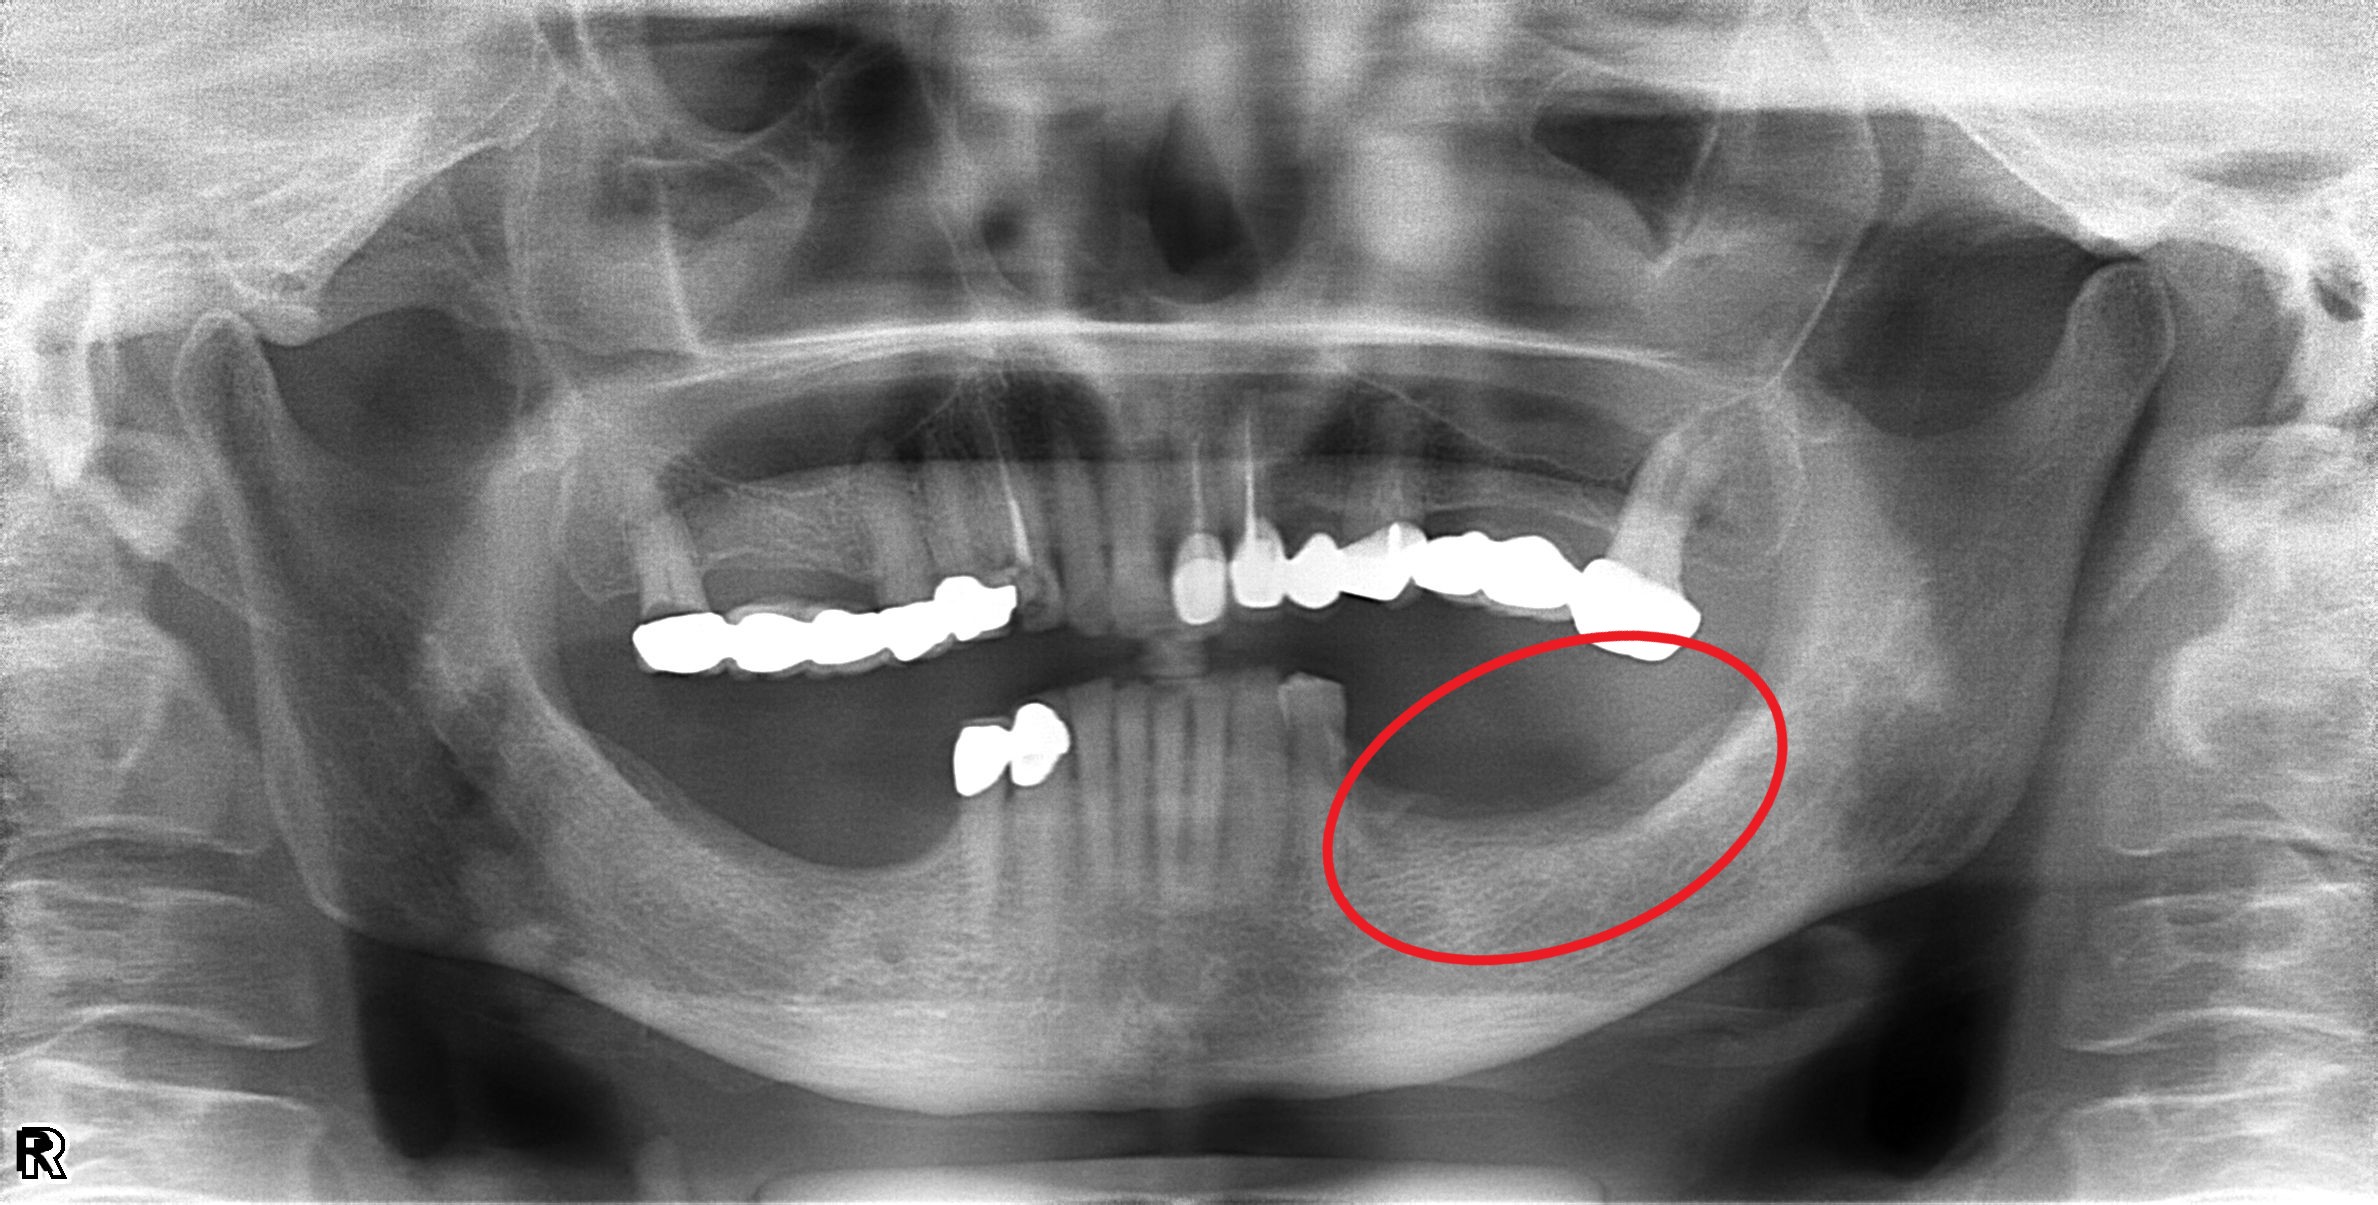

案例四

缺牙造成齒槽骨流失